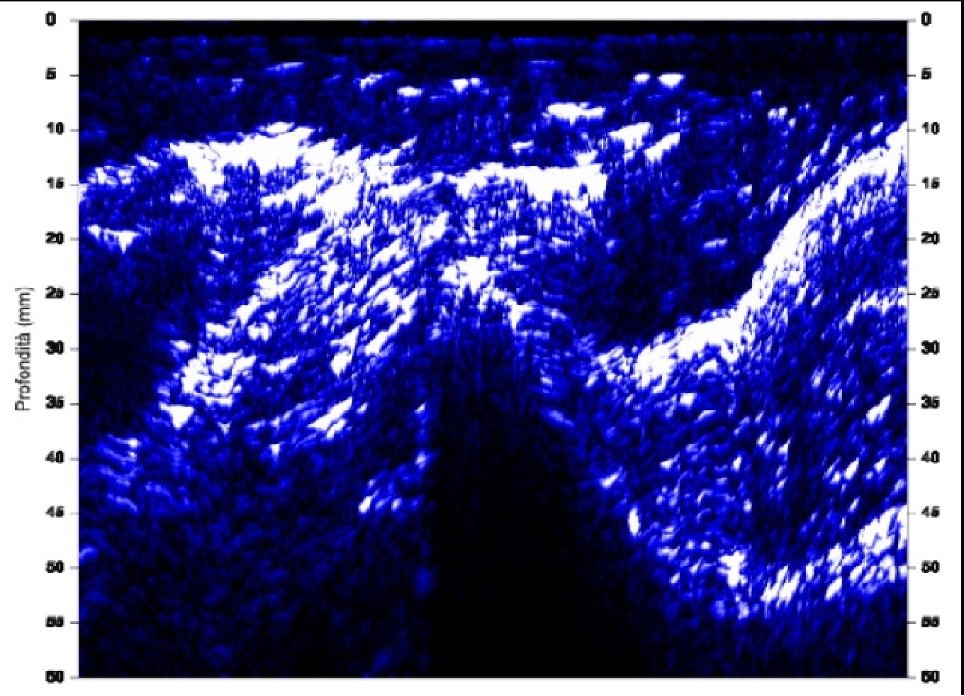

Esempio di stratigrafia su esterno coscia con individuazione degli strati dei tessuti

L’adipometro Hosand BX 2000 che utilizzo, scorrendo sulla zona di misura, crea una mappa dei tessuti sottostanti (stratigrafia), sulla quale è possibile:

L’adipometria è la metodica che permette di misurare oggettivamente, sia dal punto di vista qualitativo che quantitativo, i tessuti sottocutanei (adipe e muscolo) tramite l’utilizzo della tecnologia a ultrasuoni, in qualsiasi parte del corpo.

La misura ottenuta risulta precisa al decimo di millimetro!